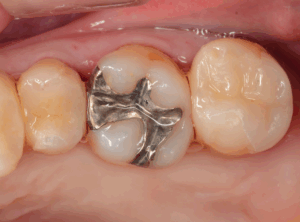

歯に優しくくっつくセラミック素材を使用した治療

セラミック治療を見た目がよい(白い)だけの治療と思っていませんか?

保険治療で使われている銀歯は金属なので経年劣化で腐食し、歯とつめ物・さし歯の間に隙間ができてしまい、そこから虫歯の再発へと繋がってしまうことが多々あります。

当院では虫歯の再発を少なくするセラミックを使用した治療をご提案しています。

セラミックは銀歯よりも歯にぴったりとくっつくため、虫歯が再発しにくいです。

また、銀歯でおこりがちな「虫歯を治したはずなのに、歯がしみる」といった症状や、アレルギー症状のリスクもずっと低い身体に優しい材料です。

セラミック治療は確かに高額ですが、身体に優しく長い目で見ると実はコストパフォーマンスの良い治療法です。

その証拠に、我々歯科医師も時には虫歯になった時。多くの先生は銀歯ではなく、セラミック治療を選びます。

お口を開けた時、銀歯で治療している先生がいたら、他の先生から少し不審に思われるかもしれません。